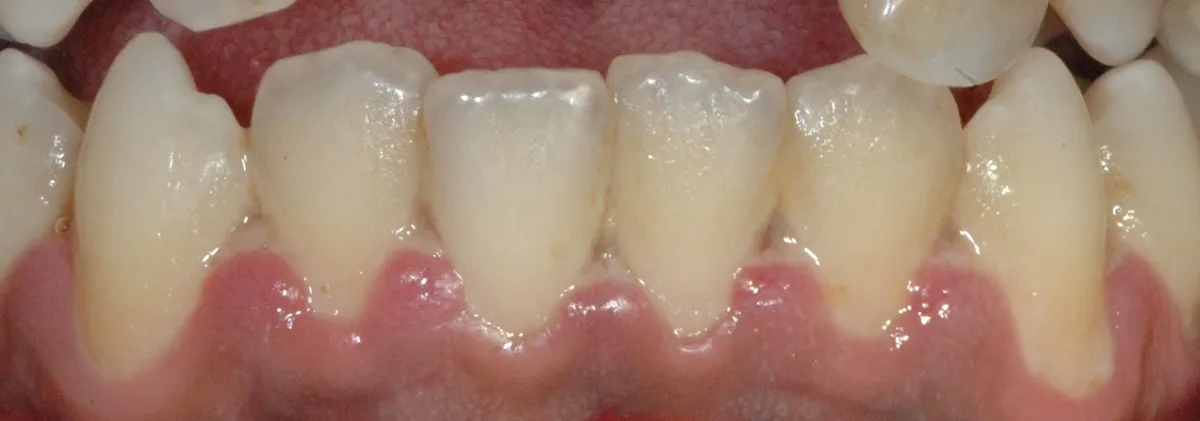

Perché le gengive si ritirano, quando preoccuparsi e cosa può fare il parodontologo. Classificazione di Cairo, innesto connettivale, lembo coronale.

Gengive che sanguinano, si ritirano o fanno male? Guida evidence-based alla diagnosi e alla cura della malattia parodontale. Studio Denti Più, Frosinone.

Innesto connettivale per recessioni gengivali: tecnica gold standard per ricostruire la gengiva e proteggere i denti esposti.

Le recessioni gengivali possono essere corrette o meno. Esistono indicazioni assolute e relative al trattamento chirurgico con copertura radicolare.